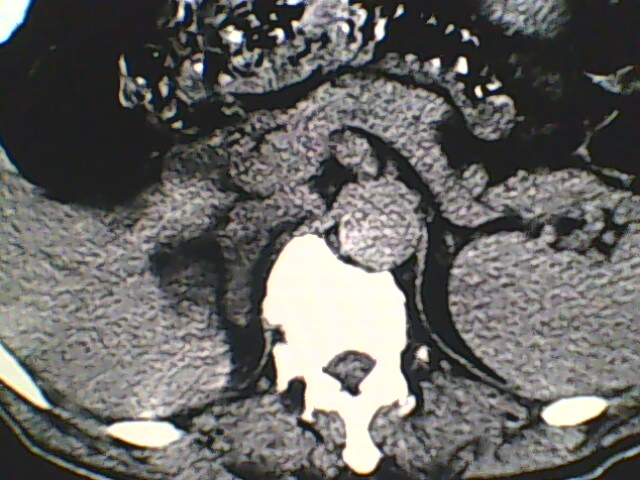

男,56岁,高血压,临床怀疑肾上腺问题,肝脏怎么那么高啊?能描述一下么?

右侧膈膨升,间位结肠,胸腰椎退行性骨关节病,右侧肾上腺可疑增生(图像颗粒太粗,窗太窄,不好看)。

支持 右侧膈膨升,间位结肠;胸腰椎退行性骨关节病;双侧肾上腺可疑增生。

楼主医院的ct机该换了。